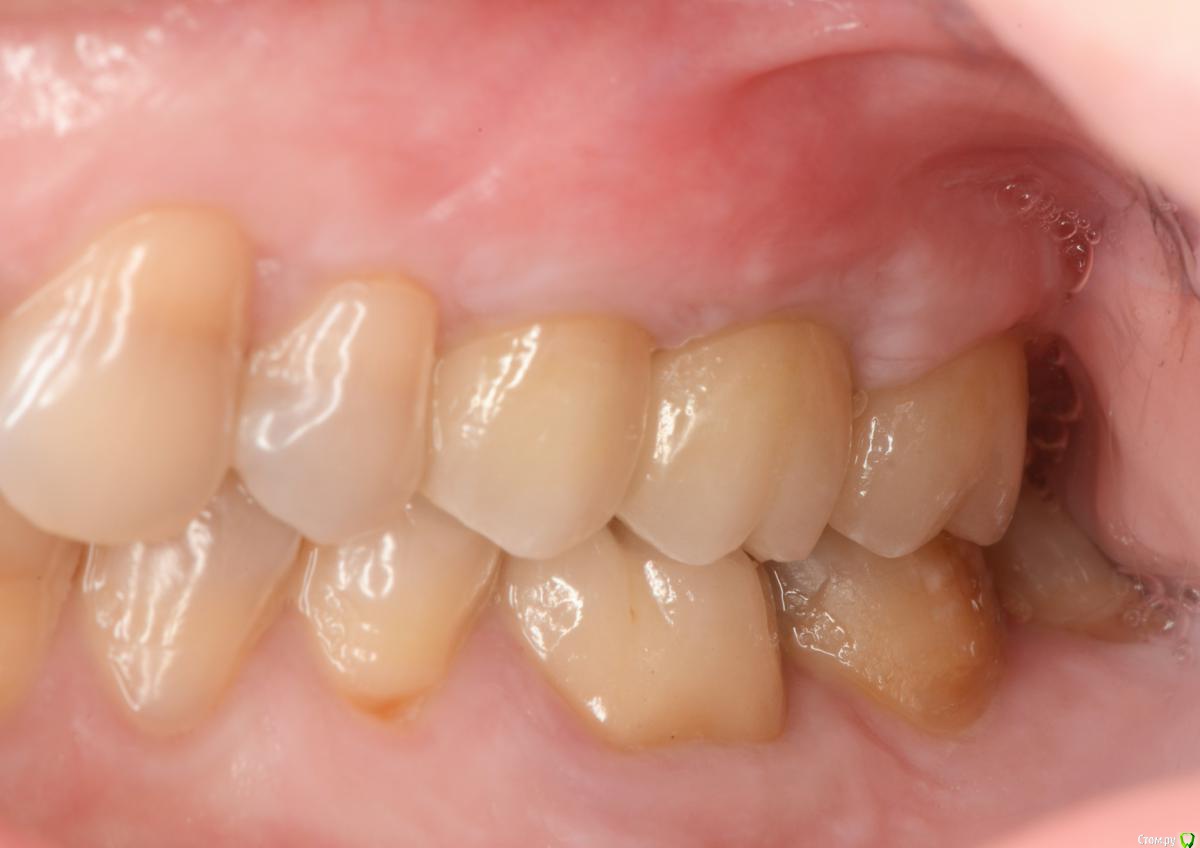

это времянки, постоянная - средний ряд, правая сторона, последнее фото

post-46374-0-27985400-1569231363_thumb.jpg